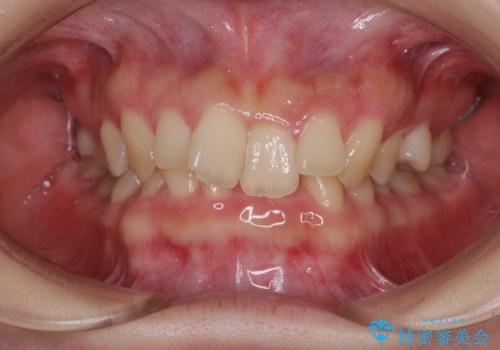

- 全体的な歯列の叢生を気にして来院された患者様です。

奥歯の咬み合わせを見ると、片方は上顎が下顎に対して相対的に前方にあり、他方は交叉した咬合の状態でした。